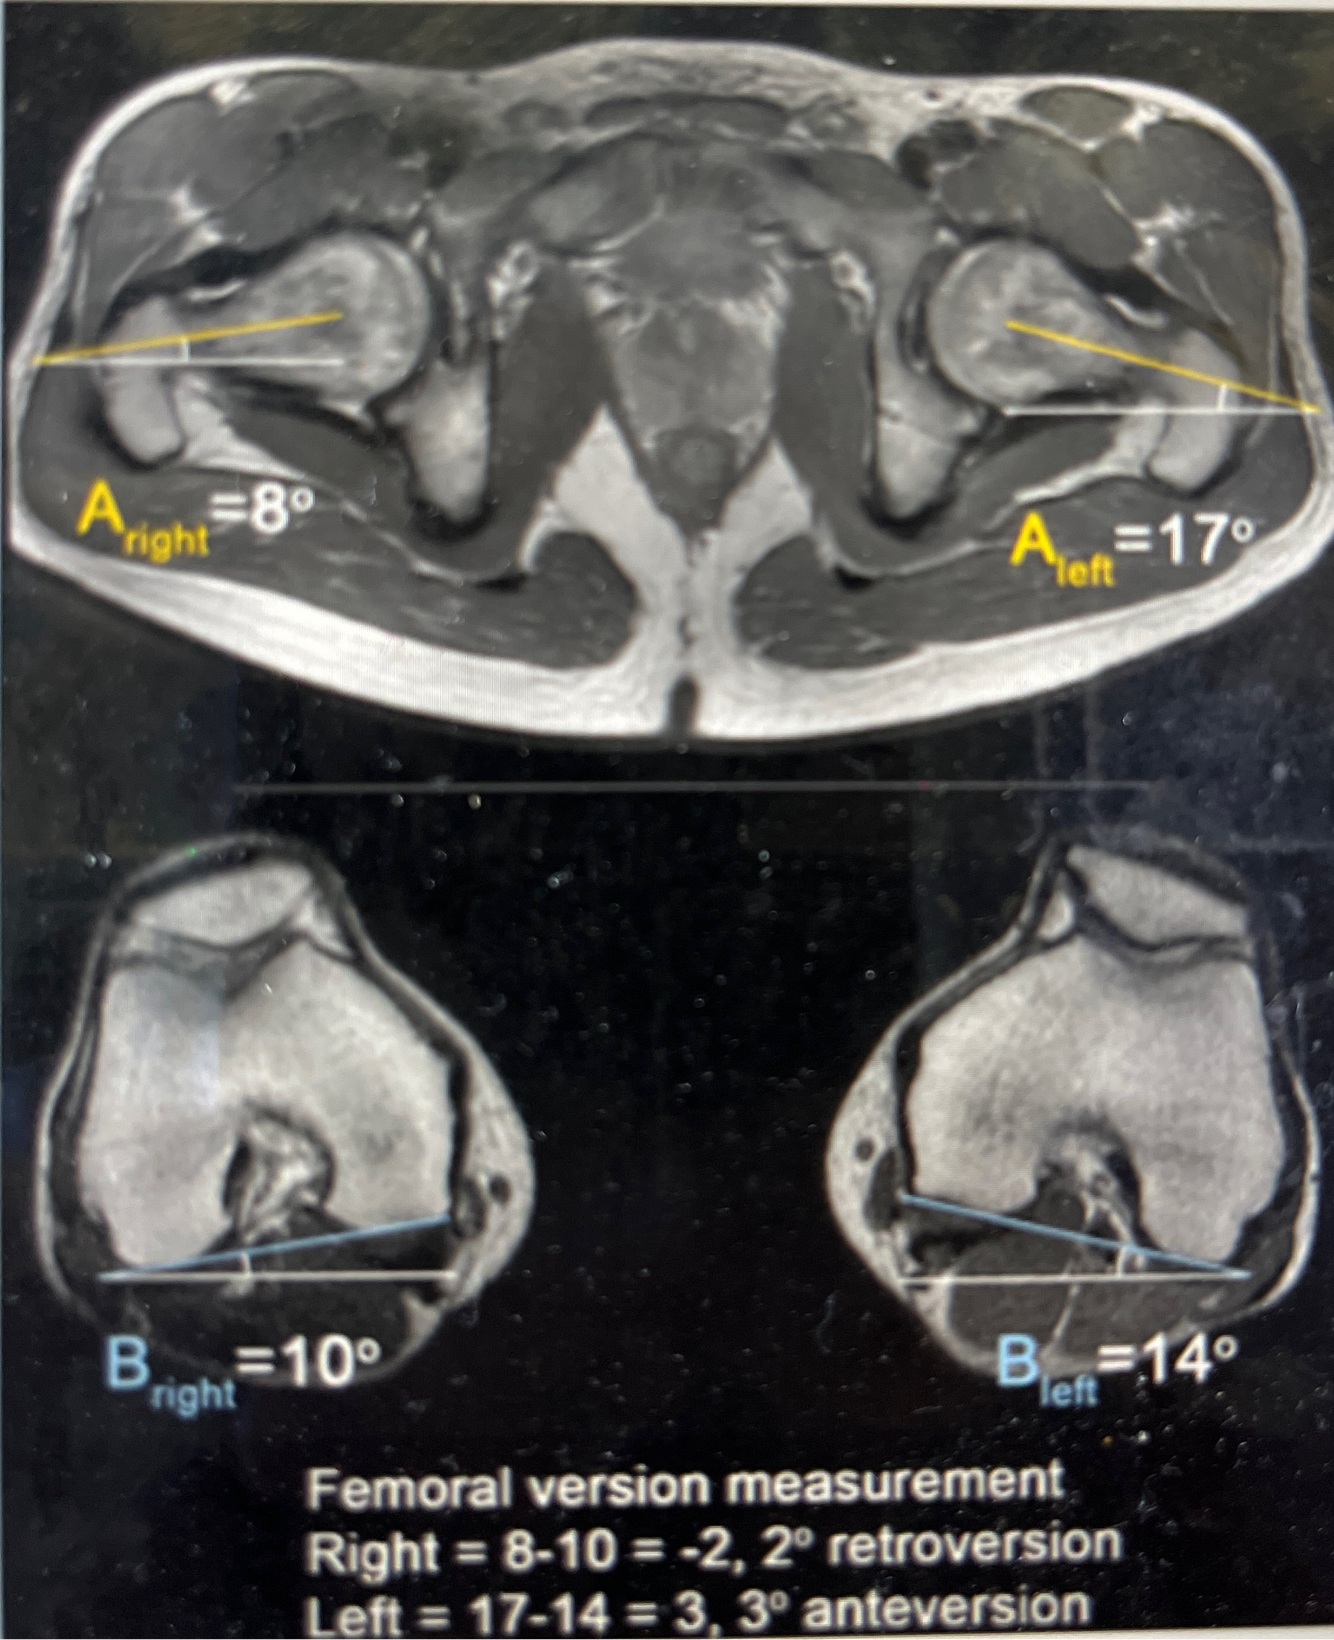

How do you calculate femoral rotational malalignment after IMN?

A

Version of hip - knee

+ = anteversion

- = retroversion